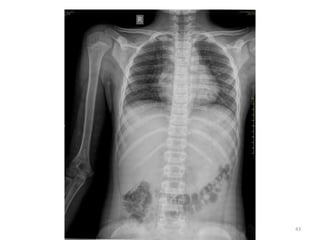

Practical issues:

• For age estimation, usually standard right sided

X-rays are taken in AP view

-with few exceptions elbow (AP and Lat)

• Selection of regions/joints:

for age 6-12 years  elbow and wrist

for age 13-16 years  elbow and pelvis

• 18.

Practical issues: • Forage estimation, usually standard right sided X-rays are taken in AP view -with few exceptions elbow (AP and Lat) • Selection of regions/joints: for age 6-12 years  elbow and wrist for age 13-16 years  elbow and pelvis • Wrist (& hand) is most studied region by foreign authors/researchers. 18